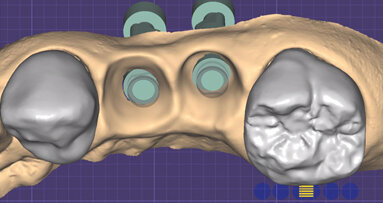

Pianificazione digitale delle procedure chirurgica, estetica e funzionale per la creazione di due arcate protesiche complete su impianti.